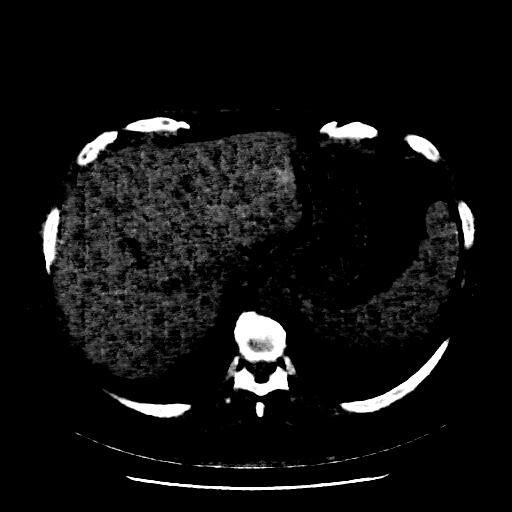

Original NATIVE CT scan (input)

Full window (WL 1023.5, WW 4095 β†’ Low βˆ’1024, High +3071)

Actual HU range: [-160.0, 240.0]